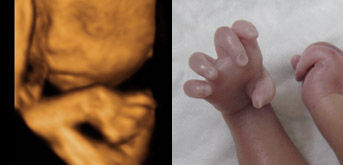

B超是利用超声波探测技术对人体脏器进行检查,没有电离辐射、电磁辐射,相对安全,因此用于对胎儿的结构进行检查就有突出的优势。B超从最早的普通B超,到彩色B超,再到今天的4维彩超。4维超声技术就是采用3维超声图像加上时间维度参数,这项技术能够实时获取三维图像,超越了传统超声的限制。它提供了包括腹部、血管、小器官、产科、妇科、泌尿科、新生儿和儿科等多领域的多方面的应用。尤其在对胎儿的产前筛查方面更是立下了汗马功劳。